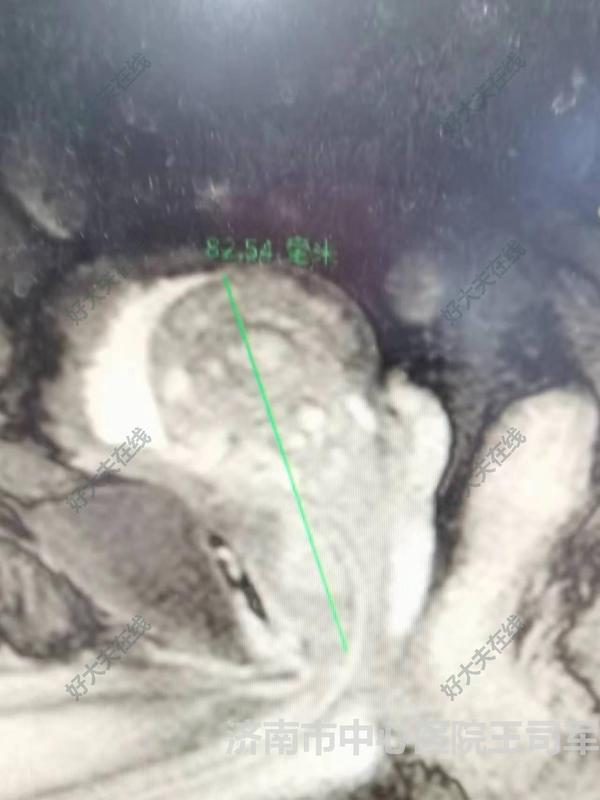

治療前 老年男性,79歲,因“尿潴留”入院。前列腺三徑約8.25*5.33*3.71cm 治療后 治療后7天 選擇1470nm激光前列腺剜除術(shù),剜除時間不到1小時,手術(shù)后無不適,恢復(fù)順利。術(shù)后7天拔出尿管,排尿通暢,最大尿流率達(dá)34ml/s